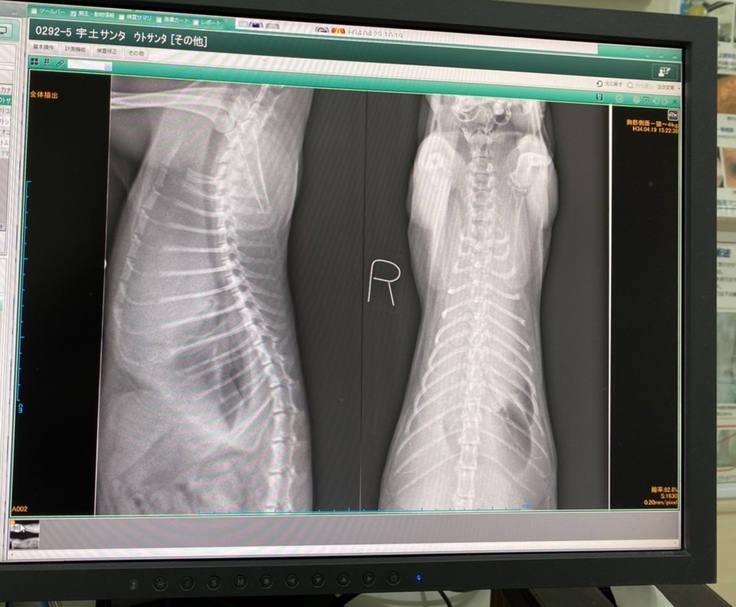

検査の結果「縦隔型リンパ腫」と診断を受けました。肺に4センチの腫瘍があります。胸水が貯留していたので、酸素吸入をしながら、胸水を抜きました。その処置をしたことで、息苦しさが改善されました。

心臓を挟んで両サイドに腫瘍が2つあるのですが、心臓の下の腫瘍がリンパ腫ではなく、胸腺腫の可能性があるとのことで、もし胸腺腫の場合は、再度治療方針が変わることもあるとのこと。

今回1回目の抗がん剤で、どれだけ腫瘍が小さくなっているかで確定診断になります。

<サンタのX線画像>